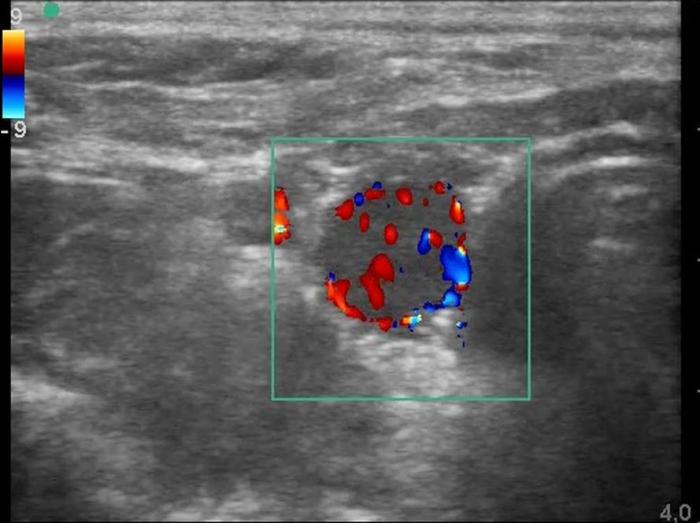

El Doppler color y espectral es especialmente útil para valorar la vascularización glandular. Un patrón de flujo periférico leve y simétrico es considerado normal. El aumento en la intensidad, desorganización o presencia de flujo central puede sugerir procesos funcionales como el hipertiroidismo o lesiones neoplásicas9.

Ecografía tiroidea en perros: glándula normal, hipotiroidismo y neoplasias

En perros sanos, la ecografía tiroidea revela una glándula simétrica, con lóbulos bien delimitados, contornos regulares, cápsula hiperecogénica fina y parénquima homogéneo, de ecogenicidad igual o ligeramente mayor al músculo esternohioideo adyacente8. Las dimensiones de los lóbulos varían en función del tamaño corporal, con glándulas más desarrolladas en razas grandes y proporciones anatómicas conservadas en todos los tamaños6. La vascularización normal observada mediante Doppler color se limita a un flujo periférico leve y uniforme, sin señales de hiperemia o vascularización central4.

Entre las neoplasias más frecuentes se encuentran los carcinomas tiroideos, los cuales suelen presentarse como masas lobuladas, de aspecto invasivo, con pérdida de la cápsula glandular, mineralización distrófica (ver Figura 8), desplazamiento o compresión de estructuras vecinas, y vascularización anómala al Doppler13 (Figura 11A-E).